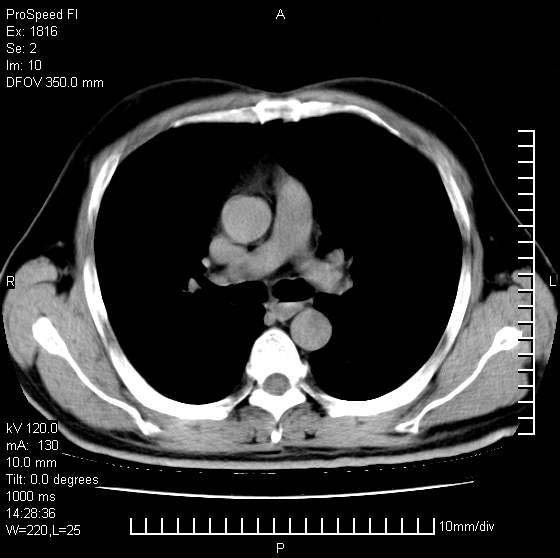

男性,50 ,肺结核9年,咳嗽,胸痛一周。右上肺见一厚壁空洞,周边有点样钙化,胸膜牵拉,洞壁较光整。诊断结核性空洞。有癌性的可能吗? 余肺野无异常,没有上传。

不像是肺ca倒更像一个结核空洞,因为看一下他内前方的支气管一点没有浸润征象只是压迫.

洞壁较厚内壁比较光整,两个病灶有关联性,纵隔淋巴结不大,考虑结核性空洞。

9年的结核应该呈现多形态病灶,该病例只能见到少许纤维索条影,似乎与结核的演变不太相符。空洞内壁不光整,外侧伴有胸膜粘连,考虑癌性空洞可能性大,期待结果。